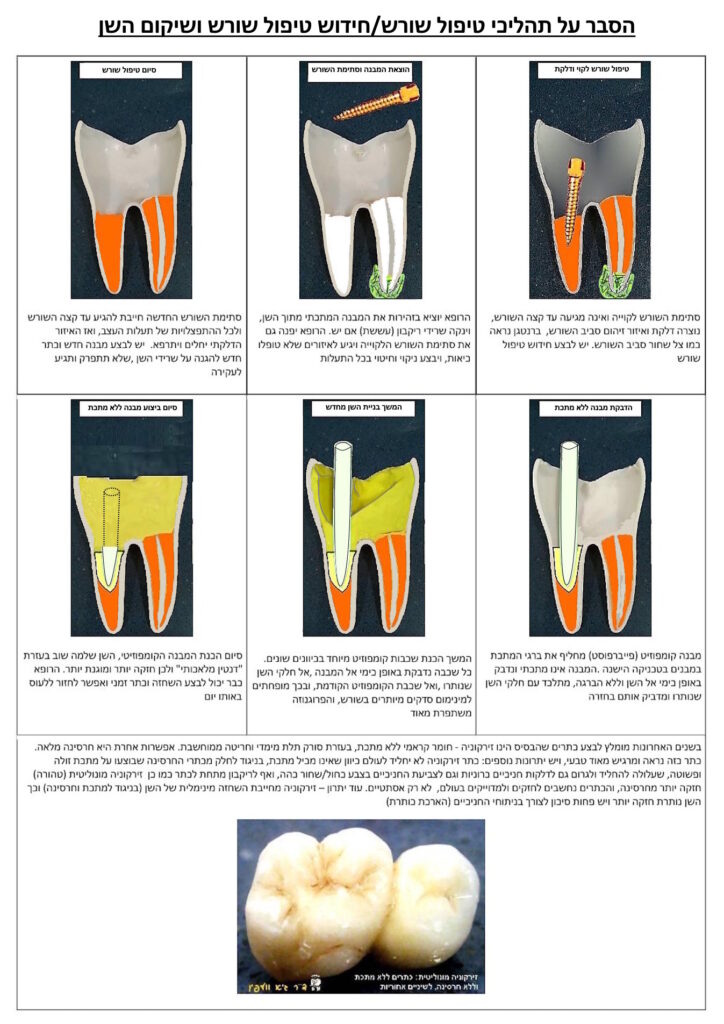

בטיפול שורש יש שני שלבים, בדרך כלל:

1. הוצאת העצב הדלקתי וכלי הדם שבתוך מוך השן (החלק הפנימי ביותר של השן) ובתוך תעלות השורש. בשלב זה גם מניחים בתוך השן חומרים מיוחדים שמסייעים להתמודד עם הדלקת ועם הכאבים.

2. ביצוע סתימת שורש אטומה ואיכותית בכל תעלות השורש, לכל אורכן ורוחבן, בכדי להשמיד סופית את כל החיידקים ולאטום בפניהם אפשרות של חזרה לתוך השן והגוף, וליצור מוקד דלקת חדשה.

* בחידוש טיפול שורש יש לבצע בתחילה את הסרת הכתר ו/או המבנה שבוצע לאחר טיפול השורש הקודם, ורק אז להתחיל בתהליך חידוש טיפול השורש, דהיינו סילוק כל החומרים הקיימים בשן, מציאת כל תעלות השורש וביצוע חיטוי מלא בהן עד למיגור הדלקת, ולסיום ביצוע סתימת התעלות בחומרים מיוחדים שמכונים "סתימת השורש".

מטופלים רבים מתוסכלים לאחר שעברו טיפולי שורש וכתרי חרסינה, והשן ממשיכה לכאוב, או שמתחילה לכאוב לאחר זמן ממושך שהייתה "שקטה". הבעיה העיקרית שבגללה טיפולי שורש אינם מצליחים ומתפתחים דלקת וכאבים הינה כישלון טיפול השורש שבוצע.

לדוגמא, אם בוצע טיפול שורש אך הרופא לא הצליח להגיע אל החלק האחרון של תעלת השורש, הרי שנותרו חיידקים וזיהום בחלק זה. שיניים שהינן בעלות תעלות שורש צרות ומפותלות, ובמיוחד השיניים הטוחנות, מועדות לכישלונות מסוג זה.

דוגמא אחרת היא טיפול שורש בשן שבה יש מספר תעלות בעצב, והרופא לא מצא את כל התעלות – ולכן באחת התעלות או יותר נותרו חיידקים וזיהום. גם כאן השיניים הטוחנות, ובמיוחד הטוחנות העליונות, נחשבות "בעיתיות" ביותר. ממחקרים מודרניים מתברר כי בערך 90% מהשיניים הטוחנות העליונות הראשונות מכילות 4 תעלות שורש, ואילו הרופא הממוצע עלול למצוא רק 3 תעלות שורש ומטפל רק בהן…

בשתי הדוגמאות הנ"ל גם אם אין כאבים והשן קיבלה כתר איכותי, הרי שמראש טיפול השורש למעשה נכשל, ולאחר זמן מה יצוצו שוב הכאבים והדלקת. ברבות הזמן חיידקים אלו שוב יתרבו וישגשגו, והזיהום שייצרו יתפשט אל קצה השורש ומעבר אליו – לעצם ולרקמות שסביב השורש. בצילום הרנטגן נראה איזור כהה, מוצלל, סביב שורש השן, שמעיד על הדלקת. במילים אחרות – כישלון של טיפול השורש.

מומלץ לבצע טיפולים מסובכים אלו ע"י רופא שיניים שהתמחה בטיפולי שורש (אנדודונט), ובעזרת מכשירים מיוחדים (שכמובן נמצאים במרפאתנו). לאחר טיפול השורש אין לאכול על השן ולהגיע בהקדם לביצוע שיקום, בדר"כ ע"י מבנה ללא מתכת (פייבר-פוסט), כתר זמני ולאחריו כתר סופי איכותי (בדר"כ זירקוניה טהורה או חרסינה טהורה או שילוב של זירקוניה וחרסינה).